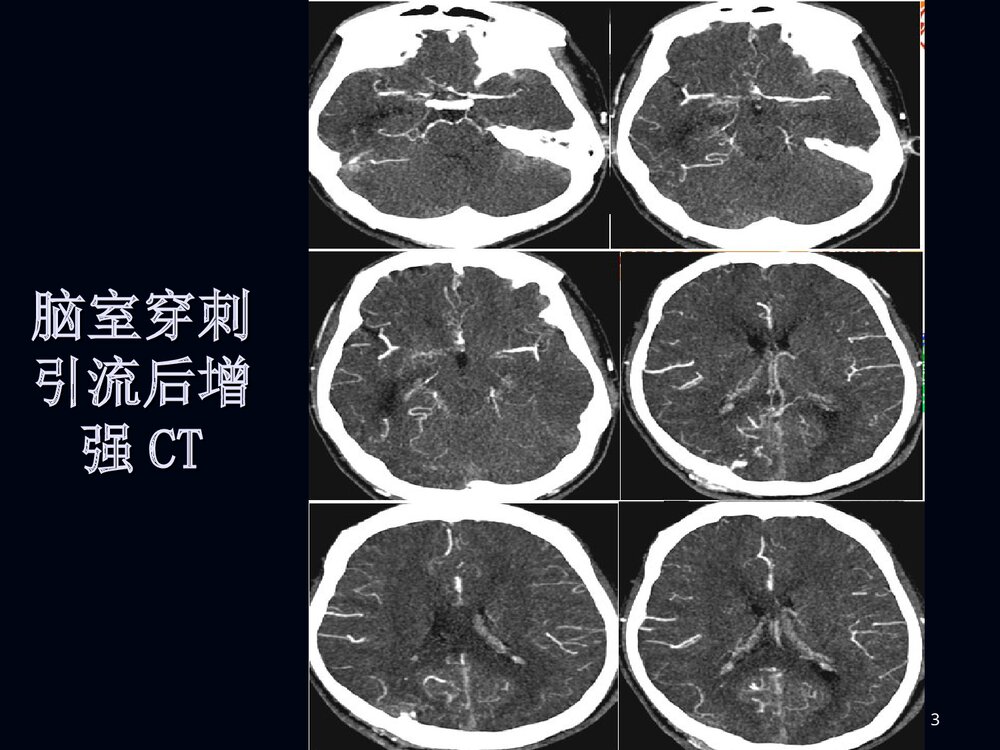

1烟雾病临床和影像诊断烟雾病临床和影像诊断2男性,男性,2020岁突发剧烈头痛岁突发剧烈头痛11小小时时3脑室穿刺脑室穿刺引流后增引流后增强强CTCT4MRIMRI5MRAMRA67病例病例22F、38Y,右侧肢体无力伴言语不清24天8MRIMRI910病例1DSA11烟雾病烟雾病病例2脑底异常血管网1213烟雾病烟雾病概述概述病理病理分型、分期分型、分期临床表现临床表现影像表现影像表现诊断诊断鉴别诊断鉴别诊断治疗治疗14概述概述烟雾病是以颈内动脉虹吸部或大脑前、中烟雾病是以颈内动脉虹吸部或大脑前、中动脉起始部缓慢的进行性的自发性狭窄或闭塞、动脉起始部缓慢的进行性的自发性狭窄或闭塞、并在脑底出现异常的小血管网为特点的一种脑血并在脑底出现异常的小血管网为特点的一种脑血管病。管病。在脑血管造影时,脑底...